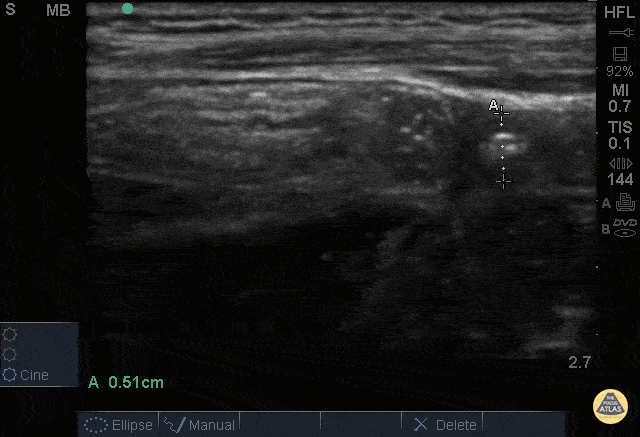

Bowel-GI - Normal Appendix - Cross Section Measured

12 y/o M with nausea vomiting fevers and vague “belly pain.” Patient mildly tender in suprapubic area. POCUS visualized a normal appendix is seen. A normal appendix is identified by a blind-ending tubular structure that is <6mm diameter measured from outer wall to outer wall (although 6mm-7mm has also been described). This patient’s appendix was measure to be 5.1mm. Dr. Sathya Subramaniam - Children’s Hospital of Philadelphia